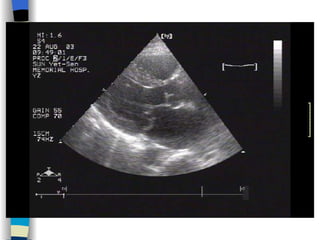

Echocardiography Establish a diagnosis, and determine the severity of AS M-mode and 2D echo  Observe aortic valve opening, thickening and calcification Helpful in determining the etiology of AS Also invaluable in detecting associated mitral valve disease and in assessing LV performance, hypertrophy, and dilatation

Doppler  echo Allows calculation of the aortic valve gradient Estimate the severity of the stenosis <  30 mmHg  Mild AS MPG  30~50 mmHg  Moderate AS > 50 mmHg  Severe AS  Color Doppler flow imaging is helpful in the detection and determination of the severity of any accompanying aortic regurgitation

Echocardiography   Confirm diagnosis, estimate severity, identify the cause 2-D echo:  Structural changes  of the valve leaflets and/or aortic root M mode echo:  Diastolic fluttering  of the anterior leaflet of the mitral valve is an important echocardiographic finding in AR Serial assessments of LV size and function Doppler echo:  Sensitive, accurate noninvasive technique for detecting AR LVOT diastolic  regurgitant  jet , estimate the severity of AR Cardiac catheterization Quantify the severity of AR Evaluate the coronary and aortic root anatomy